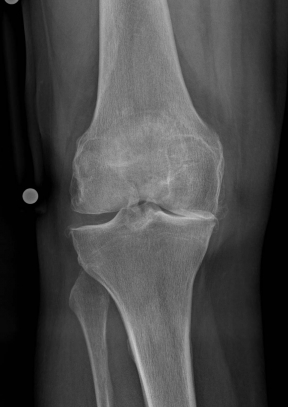

X-rays can be used to reliably diagnose the extent of joint wear. In the case of high-grade gonarthrosis, for example, the joint space and the formation of jagged edges (bone attachments, "osteophytes") as well as axial malalignment can be detected. If additional damage to the internal structures of the knee is suspected, ultrasound examination (sonography) or magnetic resonance imaging (MRI) can help clarify the situation.

Example X-ray images before and after implantation of a Persona knee prosthesis with robot.

a) präoperative Röntgenbilder des kranken Knies in 2 Ebenen | |